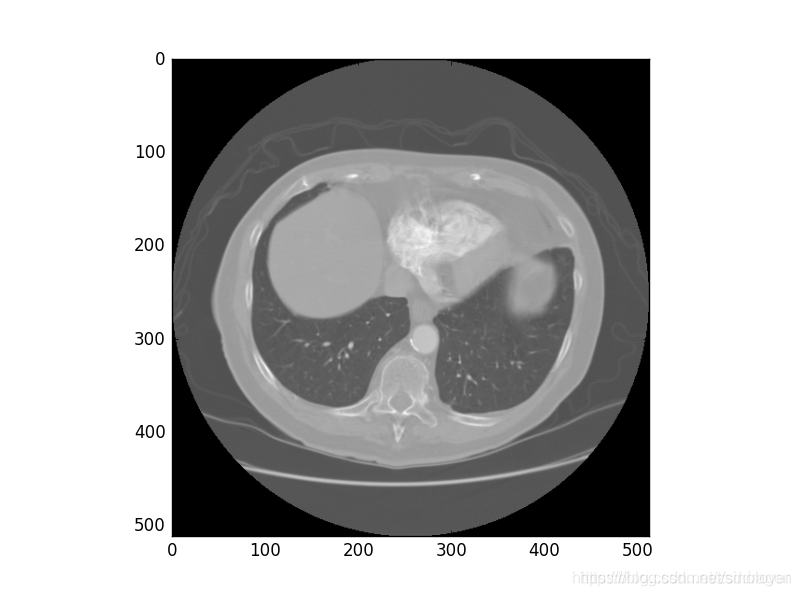

数据显示成灰度图的结果如下:

plt.imshow(img_array[0],cmap="gray")

plt.show()